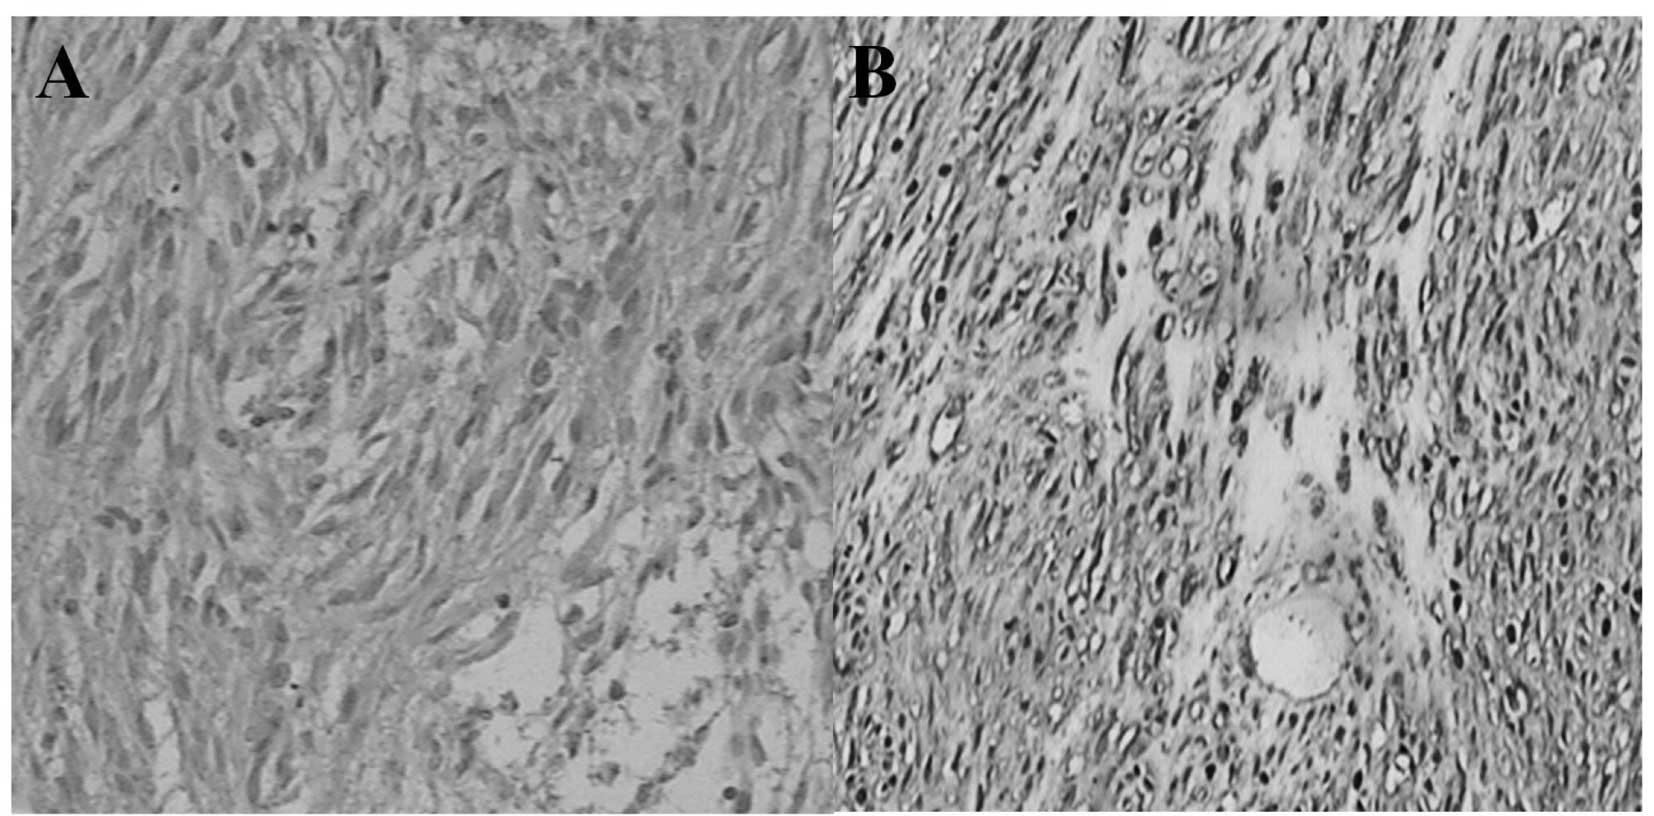

A total of 49 GIST patients (28 men and 21 women) underwent surgical resection for GISTs. Patients ranged in age from 29 to 84 years (mean, 63.3±11.8; median, 60). The tumors were located in the stomach (34 cases, 69%), small intestine (11 cases, 22%), large intestine (1 case, 2%), omentum (1 case, 2%), enterocoelia (1 case, 2%) and rectum (1 case, 2%). The tumors varied between 0.2 and 32.0 cm (mean: 12.7 ± 8.4; median: 5.0) in size. Histologically, 13 tumors were of the spindle-cell type, seven tumors were of the epithelioid-cell type and the remaining 29 were of the mixed spindle- and epithelioid-cell type (Fig. 1). Mitotic counts in 24 cases were less than 5 per 50 high power field (HPF; 49%), 13 were 5–10 per 50 HPF (27%) and 12 were more than 10 per 50 HPF (24%; Fig. 2). Ki-67 LI was classified as ‘−’ in 21 cases (43%), ‘+’ in 15 cases (31%), ‘++’ in four cases (8%) and ‘+++’ in nine cases (18%) according to the previous evaluation standards. According to the risk-grading system, one case was classified as very low grade (2%), eight cases were classified as low grade (16%), 22 as intermediate grade (45%) and 18 as high grade (37%; Fig. 3). The clinicopathological findings of the GISTs and major clinical symptoms are summarized in Table I.

Figure 1.

Histological findings in GISTs. (A) GIST, epithelioid-cell type. (B) GIST, spindle-cell type. Spindle cells proloferate in fascicles. GISTs, gastrointestinal stromal tumors.